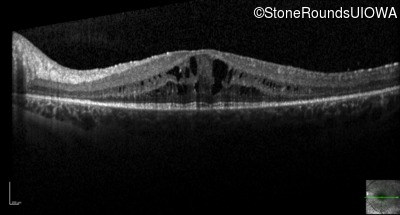

Optical Coherence Tomography - Right - 20/32 -1

Exemplar / OCT Stack

OCT Stack